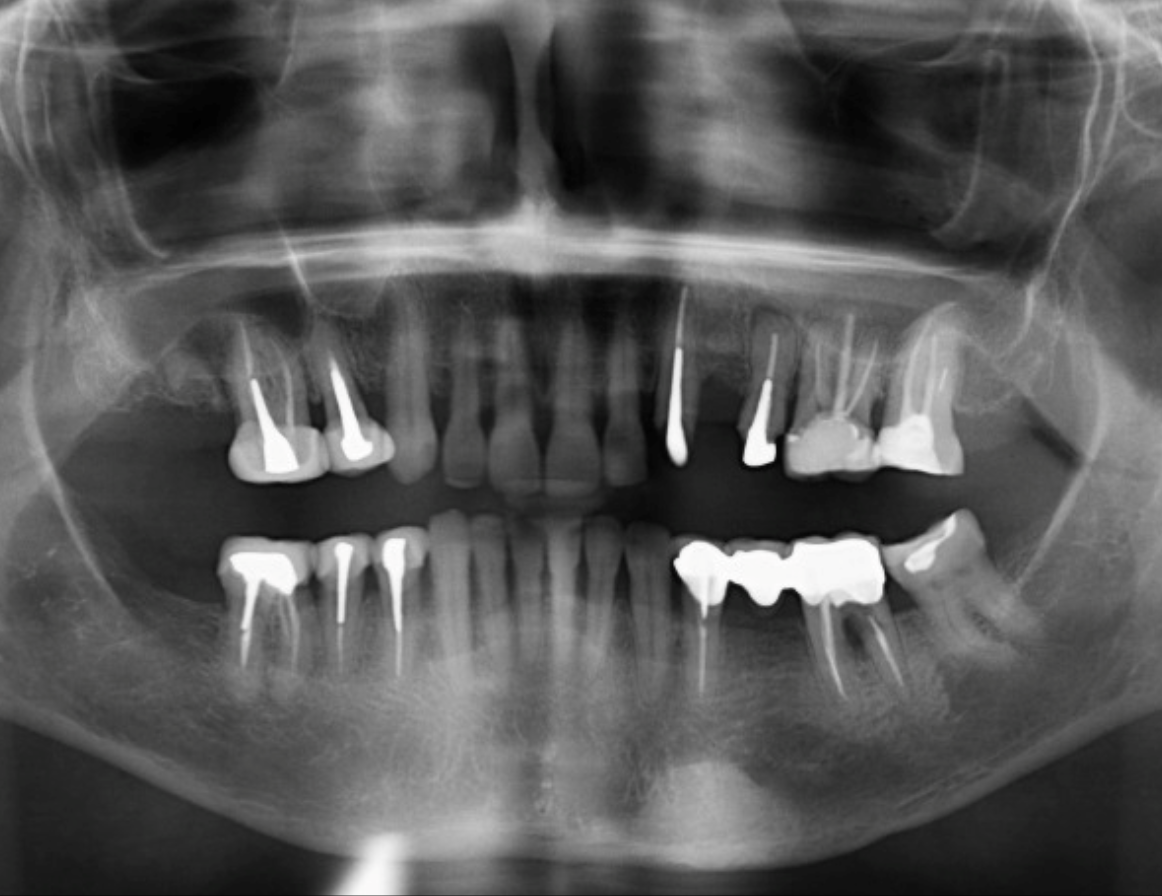

Paciente femenino de 69 años acude al Instituto para realizar una tomografía con fines de rehabilitación oral, a la evaluación de la radiografía panorámica se observa aplanamiento de ambos cóndilos mandibulares, neumatización de ambos senos maxilares, asimismo se observa la presencia de una imagen radiopaca de densidad ósea, de forma ovalada que se proyecta en cuerpo

mandibular del lado izquierdo y sobre el reborde basal. También se puede observar el edentulismo parcial de la paciente, remanente radicular de la pieza 17, múltiples piezas dentarias con corona, espigo y obturación de conductos, la pieza 25 además presenta proceso osteolítico periapical y la pieza 46 presenta proceso osteolítico interradicular y osteítis condensante circundante.

Radiografia Panorámica